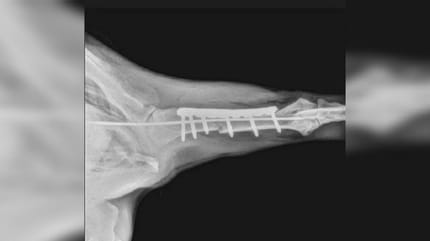

Uderzenie spowodowało, że Tana miała złamaną jedną nogę, a operacja była bardzo kosztowna — wynosiła aż 1300 euro. Lekarz z Malagi sugerował nawet eutanazję suczki.